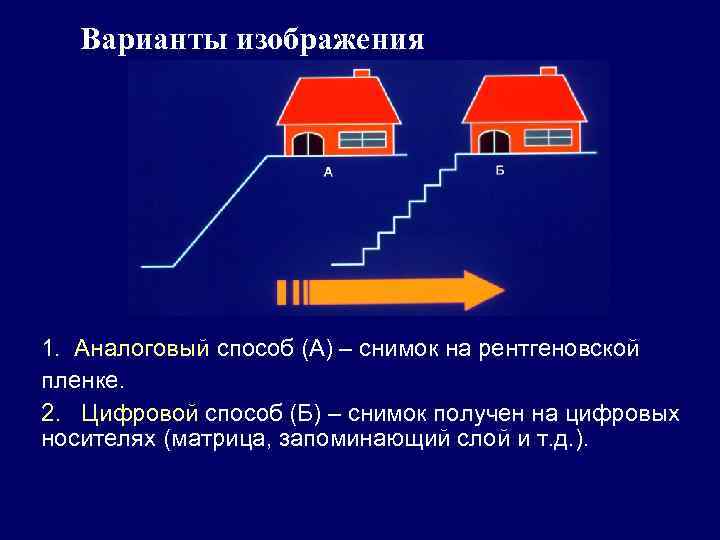

Варианты изображения 1. Аналоговый способ (А) – снимок на рентгеновской пленке. 2. Цифровой способ (Б) – снимок получен на цифровых носителях (матрица, запоминающий слой и т. д. ).